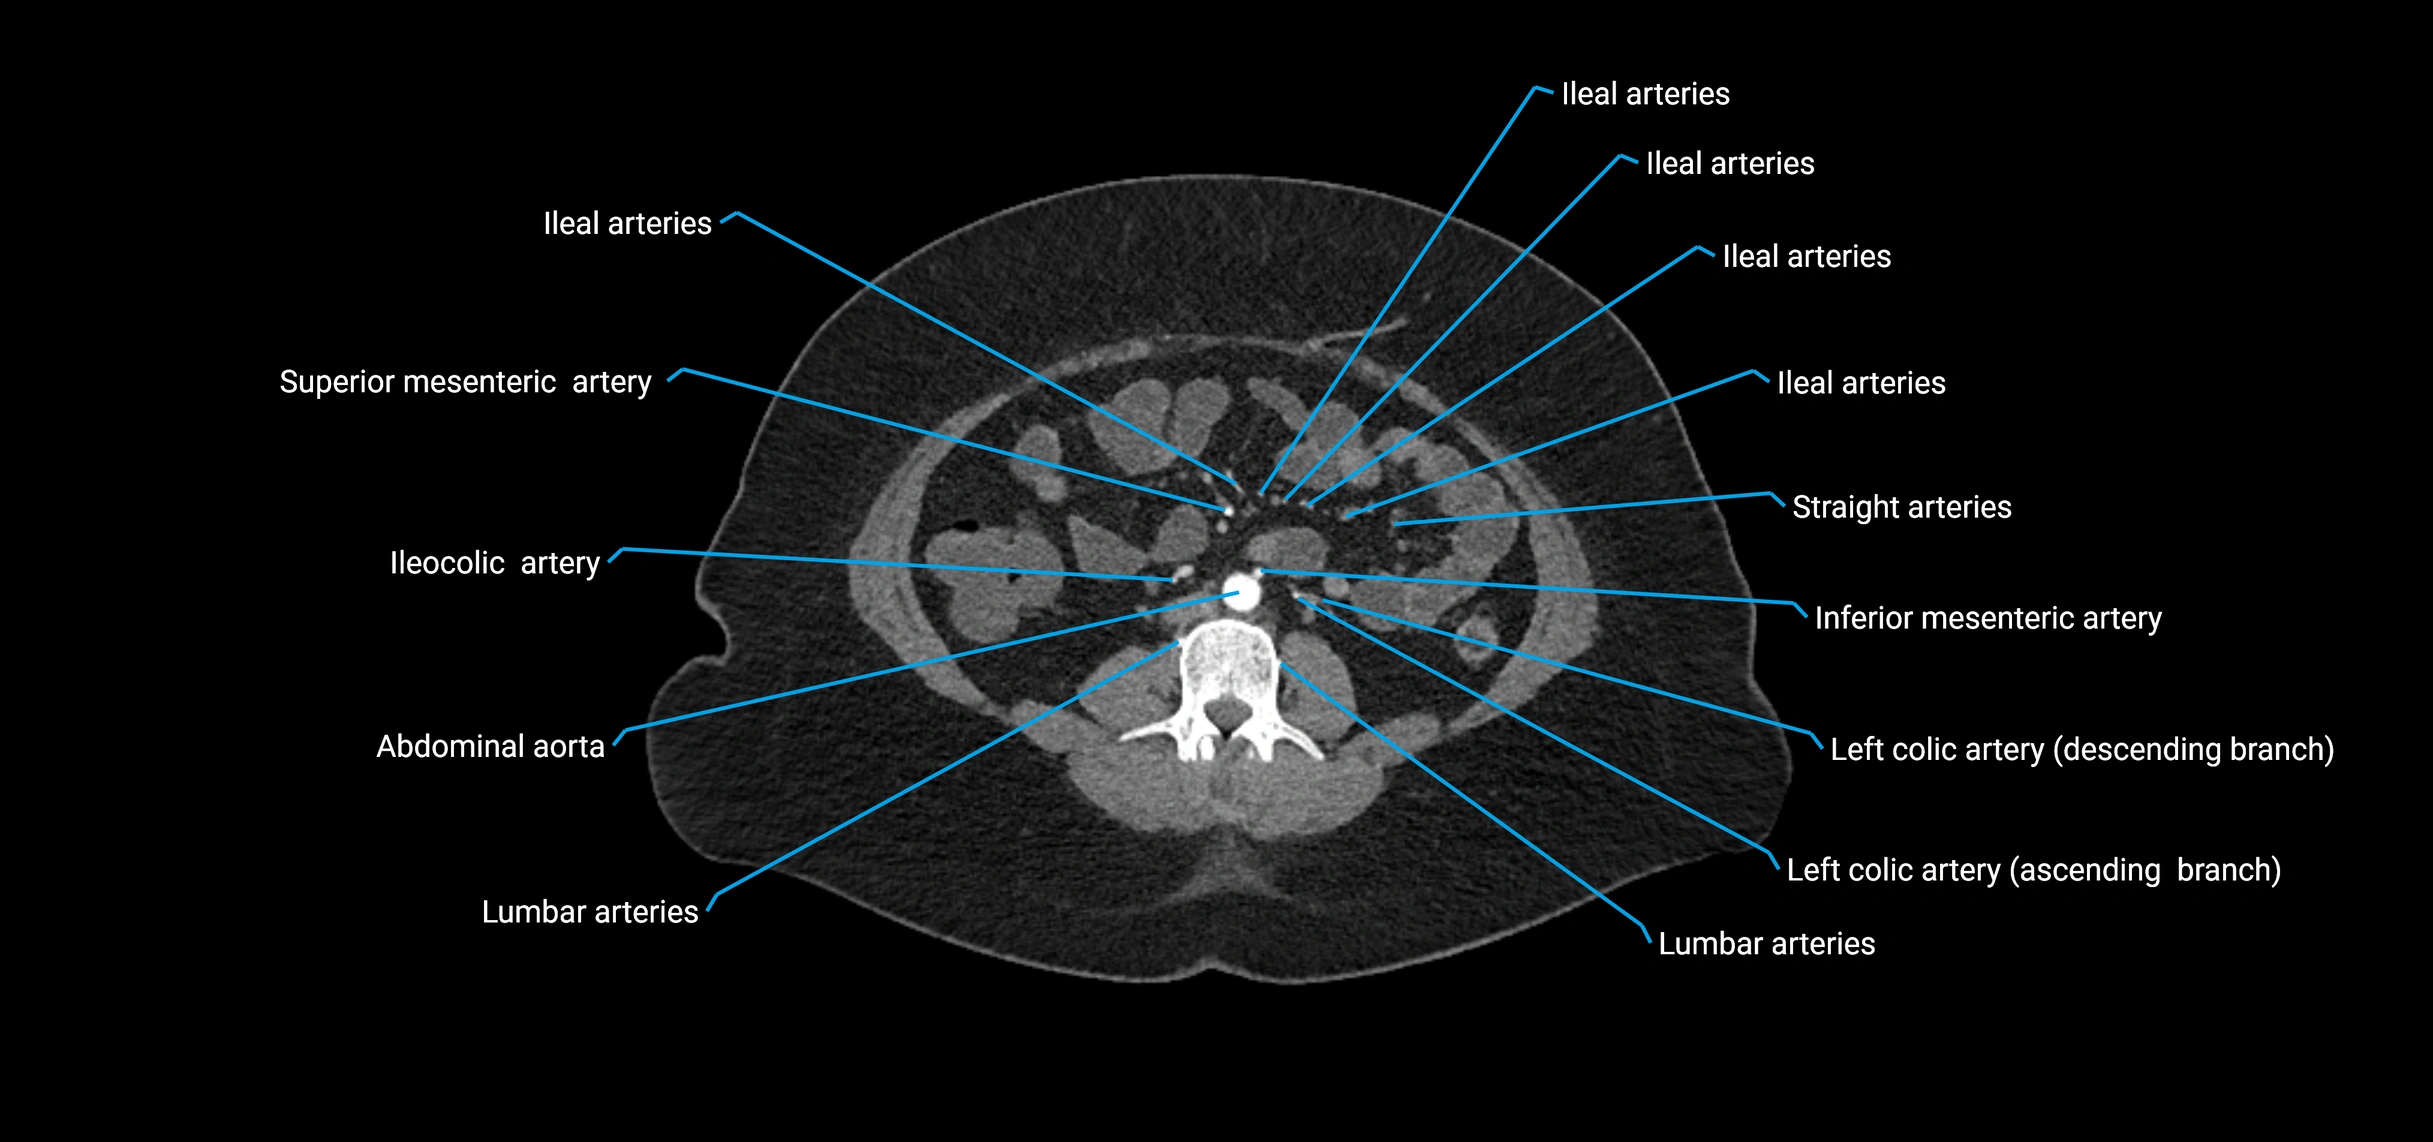

CT Appearance

Non-contrast CT:

• Appears as a tubular soft tissue structure anterior to vertebral bodies

• Calcified atherosclerotic plaques appear as hyperdense foci along the wall

• Useful for screening abdominal aortic aneurysm (AAA) size and mural calcification

Contrast-enhanced CT (CTA):

• Gold standard for abdominal aortic imaging

• Provides excellent detail of lumen, wall, aneurysm, thrombus, and branch vessels

• Multiplanar and 3D reconstructions help in aneurysm measurement, stent graft planning, and dissection evaluation

• Detects acute rupture, traumatic injury, or occlusion with high sensitivity

CT images

image